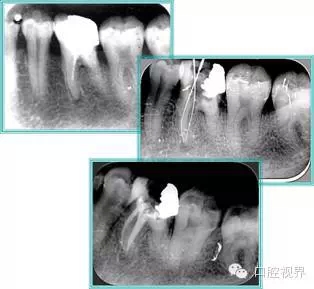

5. 不良根管充填物

常見不良根管充填物有干髓、塑化、塑化 + 根充和不良根充。

( 1 )干髓。

干髓治療時(shí),開髓后髓腔里注入甲醛甲酚 FC 灌髓,三聚甲醛固定,髓室底放置三聚甲醛緩慢釋放,進(jìn)行根管無害化處理。髓腔緩慢壞死,機(jī)體代償出現(xiàn)根管鈣化。如果患者在封閉腔出現(xiàn)出現(xiàn)病變,由于髓腔鈣化,根管堵塞嚴(yán)重,檢查治療比較困難。

解決方法:1 )徹底去除壞死的牙髓組織。 2 )借助化學(xué)性藥劑,如 EDTA 等。3 )初銼選用8#或10#K 銼,平衡力法探察到工作長度 , H銼上下提拉法使根管擴(kuò)大,提高工作效率。

左圖和上圖為干髓治療后牙齒,齲齒疏通后進(jìn)行根管充填。

( 2 )塑化。

( 3 )塑化 + 根充。

如圖為塑化加根充處理后牙齒 X 線片。